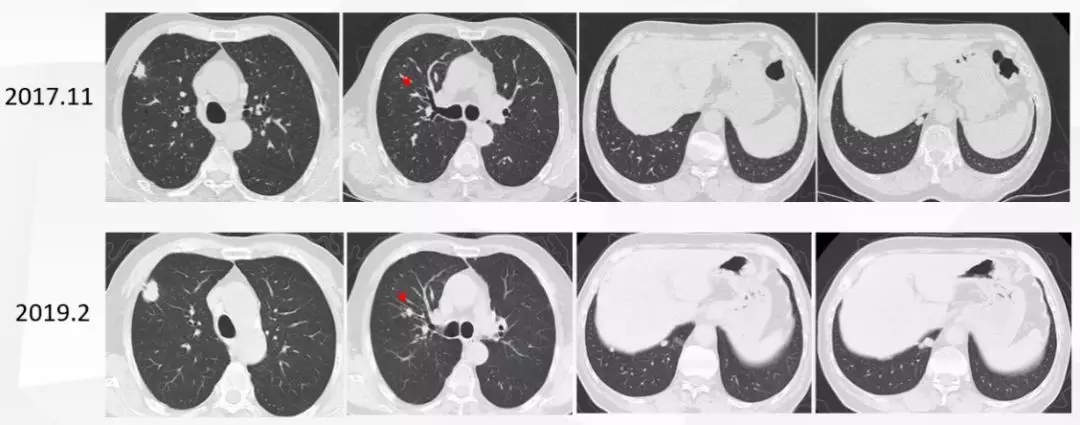

入院时肺CT显示:右肺上叶及双肺散在病灶增大,于右肺上叶出现新发病灶,提示肿瘤进展。鼻咽部MR对比,显示病变几乎消失。

图六:入我院后肺部病变评估